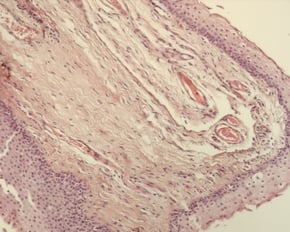

Unter dem Pterygium wird eine Gewebswucherung der Bindehaut verstanden, die auf die Hornhaut übergreift. Das Pterygium ist operabel und in der Regel gutartig, neigt allerdings zu Rezidiven. Diese Wucherung ist eine oft dreieckige Bindehautfalte im Lidspaltenbereich, die meist von der Nasenseite aus in Richtung Hornhautzentrum wächst. In ausgeprägten Fällen kann eine Verziehung der Hornhaut auftreten, die zu einer Hornhautverkrümmung führt und die Sehschärfe beeinträchtigt. In der Regel sollte man vor dem Auftreten dieser Komplikation eine operative Entfernung durchführen. Früher wurde häufig nur eine Entfernung ohne weitere Maßnahmen durchgeführt, die Gefahr eines Rezidivs war dann sehr hoch. Daher verwende ich daher immer ein Bindehauttransplantat von einer anderen Stelle des Auges, um das erneute Vorwachsen des Pterygiums zu verhindern. In besonderen Fällen wird auch zusätzlich ein wachstumshemmendes Medikament während der Operation verwendet.